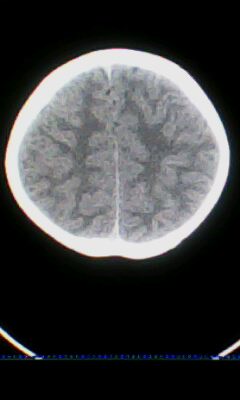

标题: PED3324:男 10岁 右侧 眼不自主抽动 自感颈部不适 [打印本页]

标题: PED3324:男 10岁 右侧 眼不自主抽动 自感颈部不适

蛛网膜下腔出血。

蛛网膜下腔出血可能。

颅脑ct轴位平扫颅内未见明确异常;建议必要时行mri检查。

窗调的不好,图像感觉怪怪的,不好说有什么明显异常,可建议mri检查。

颅脑ct轴位平扫颅内未见明确异常。